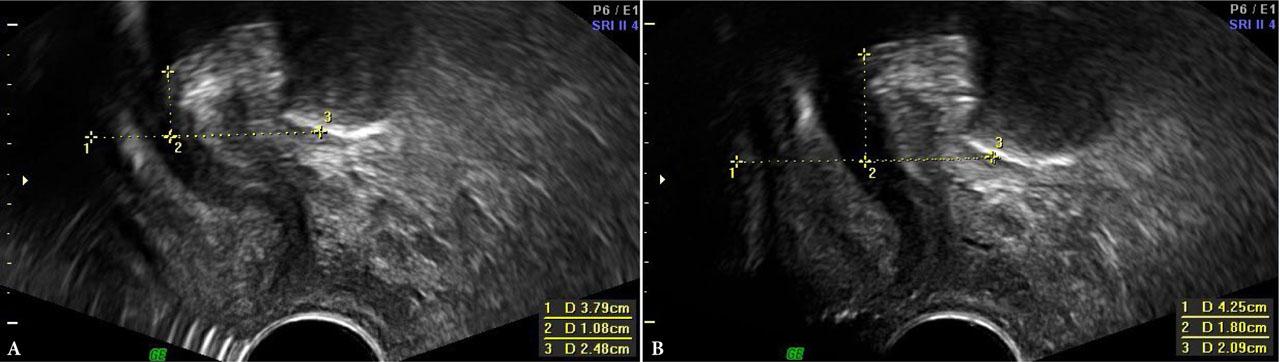

PFU-TA and PFS-TV were performed by another specialist with extensive experience in both techniques, who was blinded to MOS findings. Ultrasound was performed on the GE Voluson 730 PRO and GE Voluson 730 EXPERT systems, using the GE RAB4-8L Convex 4–8 MHz transabdominal probe and the GE RIC5-9E 5–9 MHz transvaginal probe. LAM assessment and urogenital hiatus measurements were performed on an empty bladder, at rest and on maximum PFMC, using 4D imaging, following a technique described by Dietz (PFU-TA)(18,19). The analysis included differences in hiatal area, circumference, transverse and longitudinal dimensions (A, C, T, L, respectively), measured at rest and during PFMC. The values of ΔH, ΔD and vector = √ (ΔH2 + ΔD2), obtained in PFU-TA and PFS-TV imaging, were used to assess the ultrasound parameters of urethral mobility(20,21) (Fig. 1).

PFS-TV – measurement of urethral mobility parameters at rest and on PFMC. A. At rest. B. On PFMC. 1 – horizontal axis; 2 –H; 3 –D